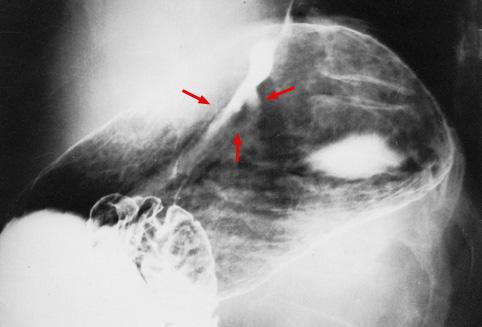

질환(병리주체)의 분류 악성 상피성종양/선암

부위(장기별) 위(부위)/분문

검사방법 X-P

종양의 육안분류 0형(표재형)/IIc형(IIc)

종양의 최대경(밀리미터) 10~14

종양의 심달도 m